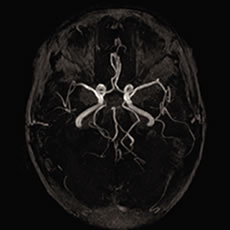

以前はカテーテル(管)を脳の動脈に挿入して薬剤を注入していましたが、この治療はカテーテル操作などの治療技術習得が必要なため、限られた施設でしか 治療できませんでした。t-PAは通常の注射(静脈内投与)で治療が可能であり、特殊な技術が必要ないのも特徴です。図1はt-PAによる回復例です。

![]() |

| 図1)t-PA投与後のMRA。 右中大脳動脈が再開通して末梢部が摘出されている |